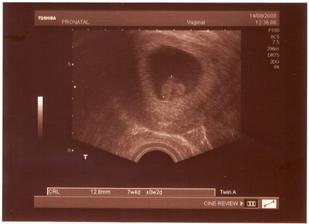

14.08. 2008 - další UTZ v Pronatalu, plod má 12,8mm a srdíčko bije jako zvon. Jsme 7+4, TP vychází na 29.3.2009